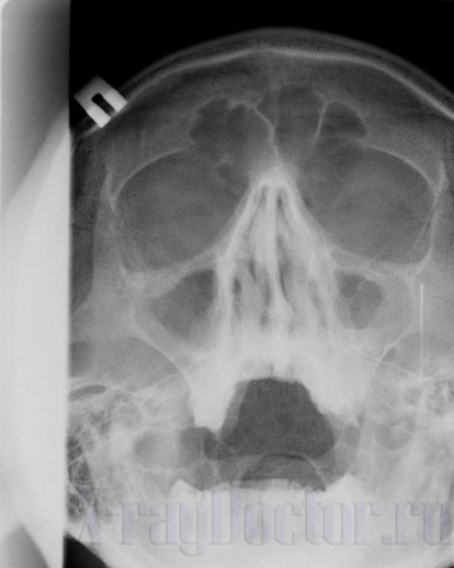

Рентгеновский снимок показывает синусит на начальных стадиях. Этим и объясняется использование рентгенографии при исследовании состояния придаточных пазух носа.

При синусите врачи выявляют на снимке снижение пневмотизации пазух с горизонтальным уровнем в средней трети. Такая рентгеновская картина является классической.

Отечно-катаральная форма заболевания на начальных стадиях проявляется подушкообразным выпячиванием слизистой оболочки. На снимке при этом типе болезни прослеживается булавовидное утолщение ткани. Такая рентгеновская картина наблюдается в острой фазе заболевания.

Снимок с хроническим синуситом (двусторонние пристеночные наложения)